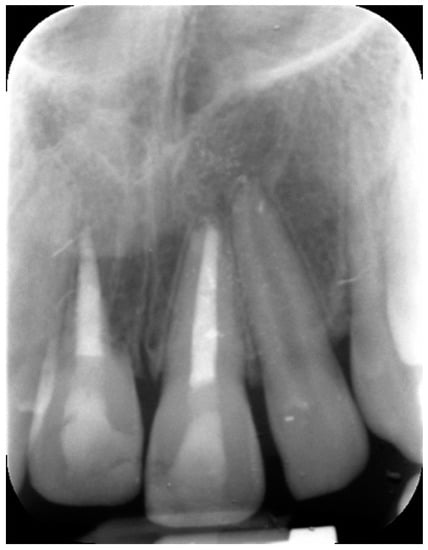

External Root Resorption Management of an Avulsed and Reimplanted Central Incisor: A Case Report

2. Case Report